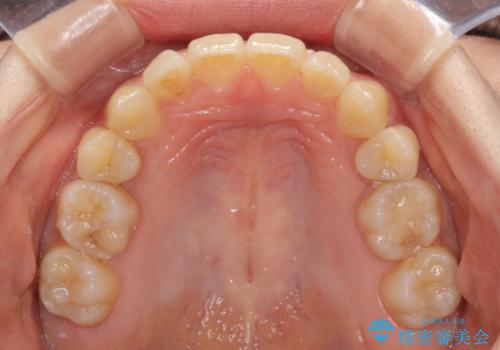

奥歯の反対咬合 上顎骨を拡大してインビザラインで矯正

- 奥歯の反対咬合を気にして来院された患者様です。

反対咬合は上顎骨の幅が下顎骨よりも小さいことが原因なので、拡大装置により骨幅を広げて上下関係を改善し、その後インビザラインにて歯並びを整えることとしました。